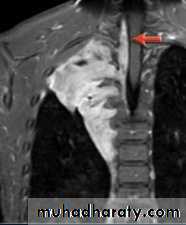

• Neurogenic tumours are by far the commonest cause of posterior mediastinal masses. Pressure deformity of the adjacent ribs and thoracic spine is often visible.

MRI is used only in highly selected cases, 1- where CT contrast agents are contraindicated or 2-demonstrating the relationship of a posterior mass to the spinal canal

Posterior mediastinal mass